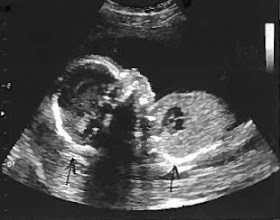

| {twenty lovely weeks} |